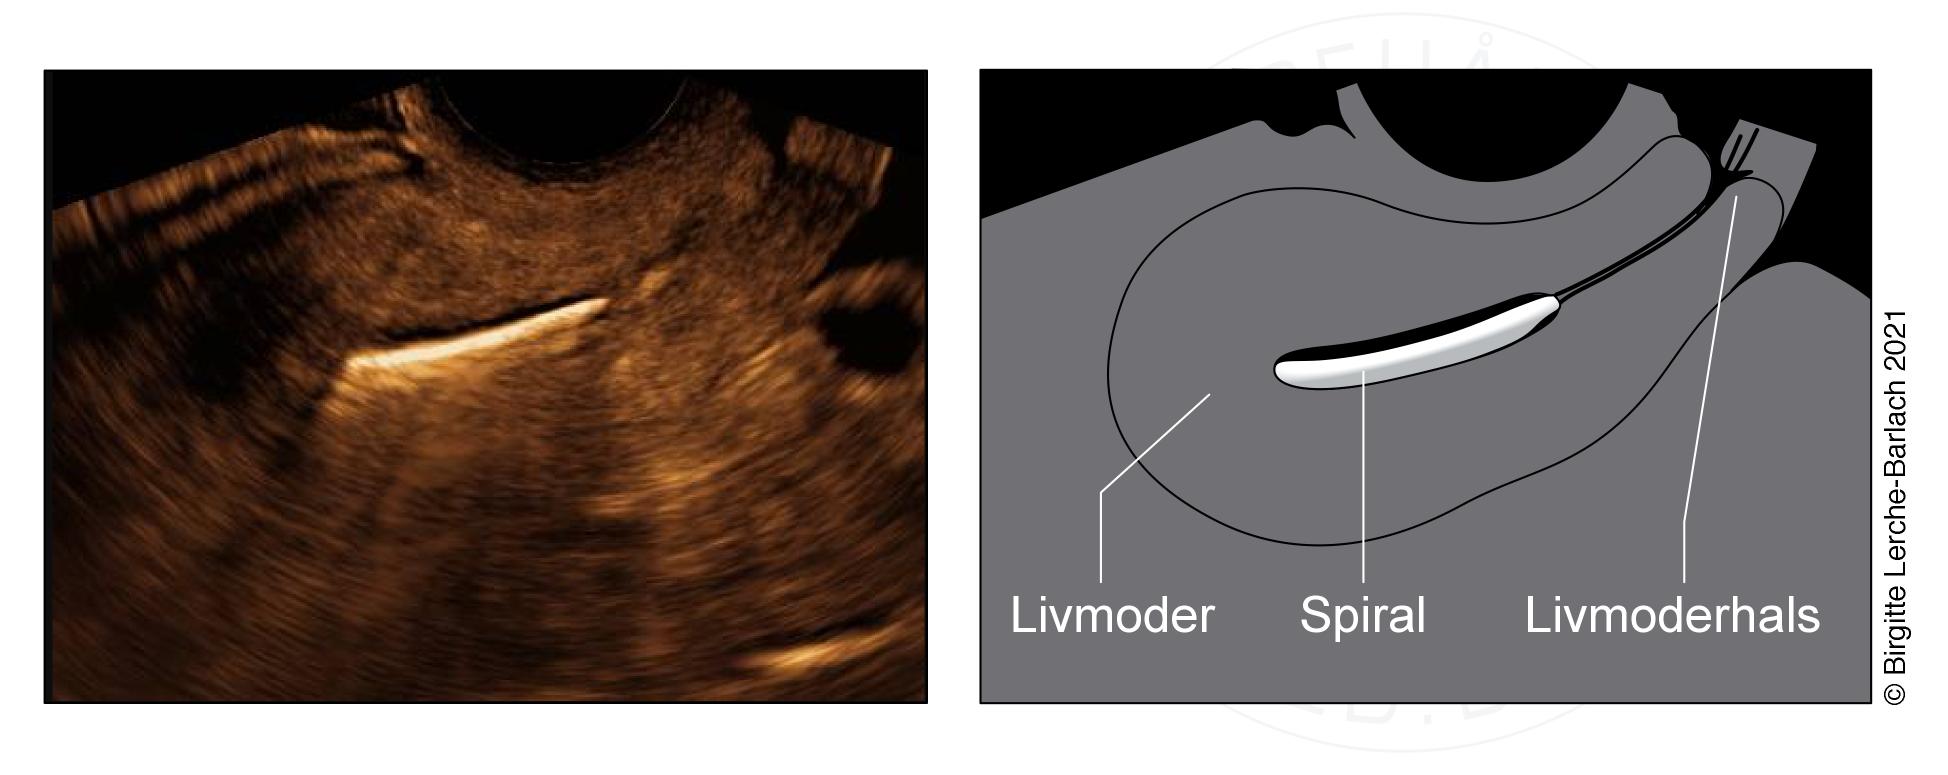

Ultralydskanning der viser kroppen af en kobberspiral (den kraftige hvide linje) inde i livmoderhulen.